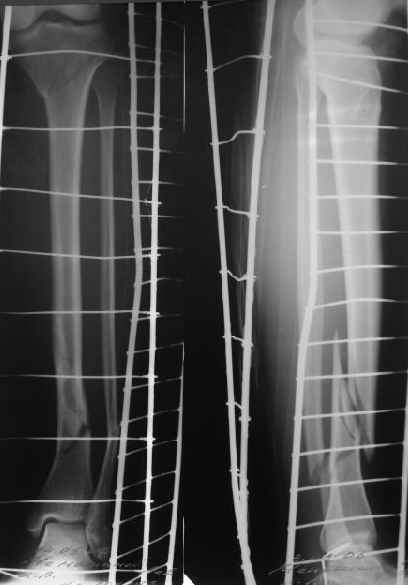

Проксимальный и дистальный переломы tibia

Направили к нам пациентку 35 лет с переломом дистального отдела костей голени.

У нас сделали снимок сзахватом обоих суставов - еще и проксимальный метафиз сломан. Чем бы у вас фиксировали такой перелом? Как его правильно закодировать по классификации АО?

Наверно, лучше всего по Илизарову.Что-то похожее я соперировал лет7-8 назад.Как кодировать по АО не знаю. А вообще зачем нужна кодировка по АО?

I don't know about the coding, but this looks like an ideal case for Ilizarov fixator.